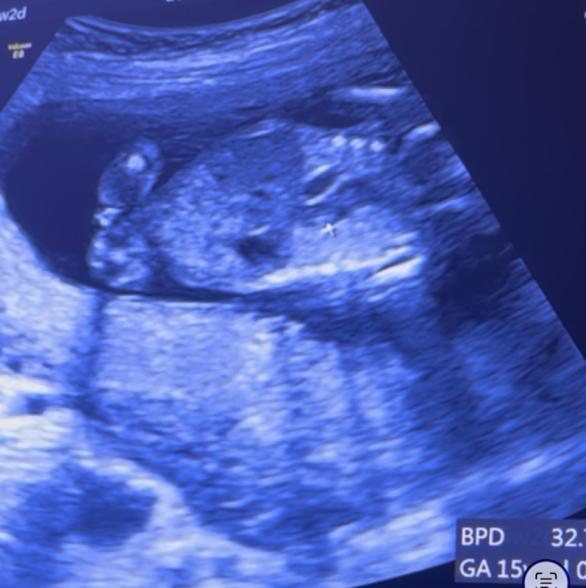

現在15w2dの妊婦です。 今回検診でおそらく女の子かなーと言われましたが 1つ目の写真は今お股になにもないように見えますが 2つ目の写真にはシンボルがついてるのかな?とも思います。 男女どちらの可能性が高いか、 今の時点での宮川先生の見解をお伺いしたいですm(_ _)m

2枚目のお写真で、確かに足の間に何かありそうにも見えますね。

臍の緒の可能性もないかなと思いました。

また斜めに走る2本の白い線は、両足それぞれの内側の線にあたるのではないかとも思いました。

写している角度で、下側から見ている画像でもないかと思いました。

女の子可能性は高そうに思いましたが、また次回の健診の際にかかりつけの先生にもご相談いただけたらと思います。